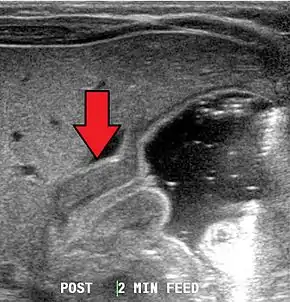

Pyloric stenosis as seen on ultrasound in a 6-week-old[13]

Most cases of pyloric stenosis are diagnosed/confirmed with ultrasound, if available, showing the thickened pylorus and non-passage of gastric contents into the proximal duodenum. Muscle wall thickness 3 millimeters (mm) or greater and pyloric channel length of 15 mm or greater are considered abnormal in infants younger than 30 days. Gastric contents should not be seen passing through the pylorus because if it does, pyloric stenosis should be excluded and other differential diagnoses such as pylorospasm should be considered. The positions of superior mesenteric artery and superior mesenteric vein should be noted because altered positions of these two vessels would be suggestive of intestinal malrotation instead of pyloric stenosis.[7]